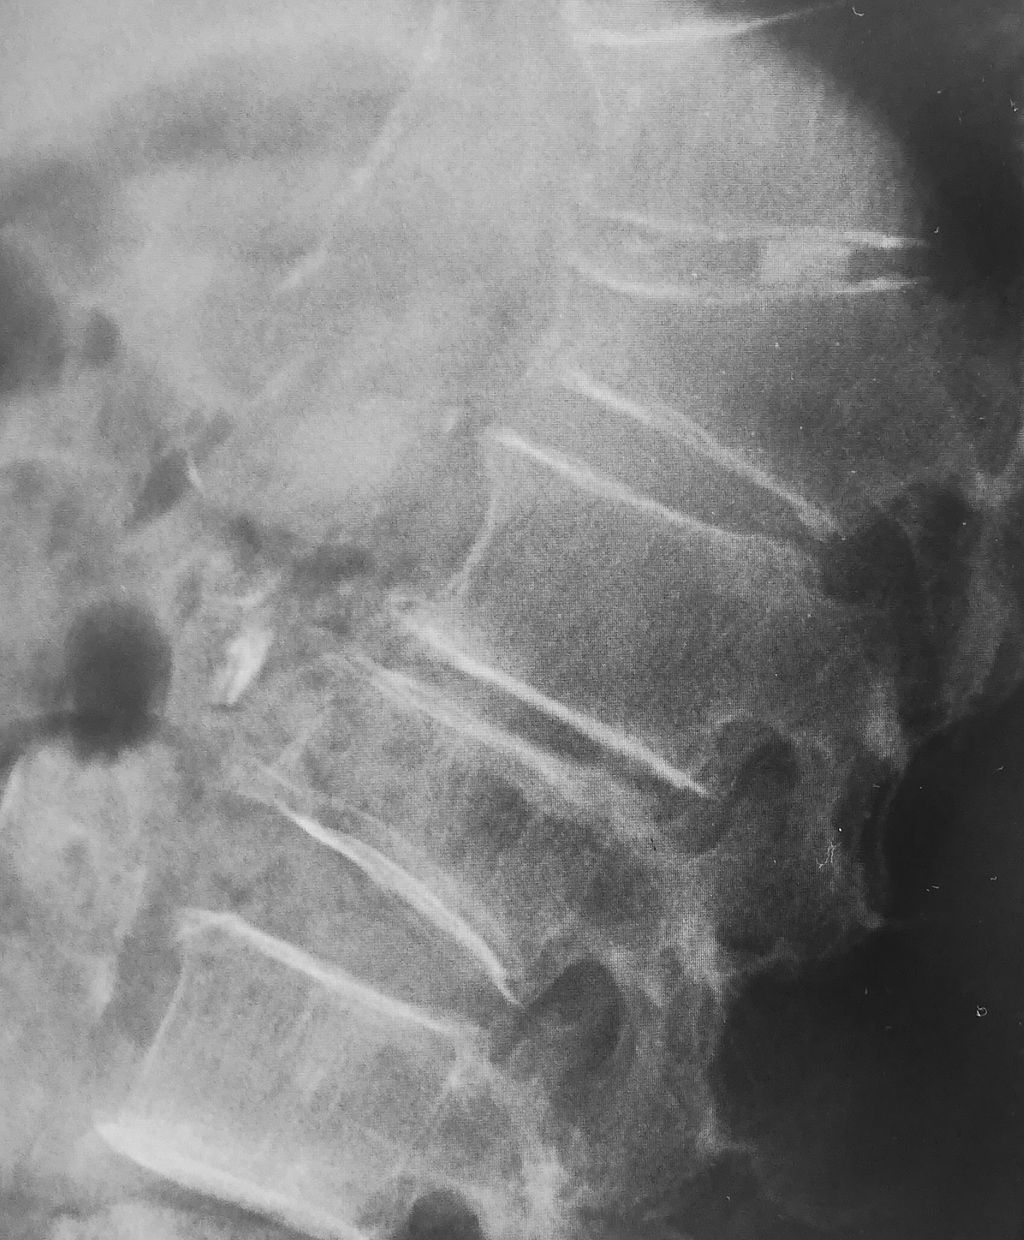

この患者さんは、骨粗鬆症が高度のためにいくつかの脊椎に圧迫骨折を併発しています。見た目にも円背であり、脊椎アライメントは著明な後弯変形しています。

円背のために腹腔容積が減少します。腹腔容積が減少すると、腹圧が高まって逆流性食道炎を併発し、膀胱内圧が高まるために失禁を併発します。

一方、腹腔容積が減少することで胃の容積も減少するため、今回の症例のように以前と比べてお腹が膨れて食事量が落ちるということも併発します。